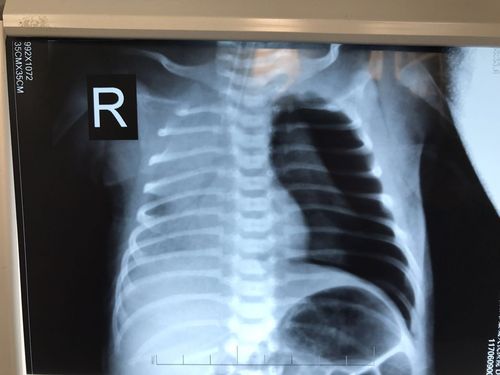

新生儿科成功抢救一例呼吸窘迫综合症并发大量气胸患儿

立即完善床旁胸片,提示右侧大量气胸(图2).